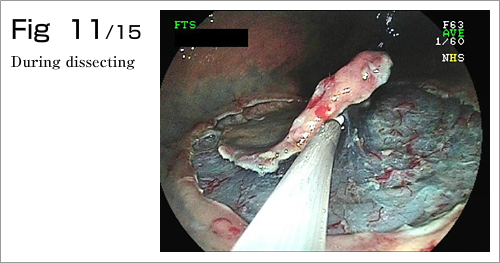

The procedure is done in several steps. First, the margins of the lesion are marked by electrocautery, and then a submucosal injection is used to lift the lesion (Diagram 4-8). After which, a circumferential incision into the submucosa is made around the lesion (Diagram 9). Finally, the lesion is dissected from underlying deep layers of GI tract wall with electrocautery knife and removed (Diagram 10-13). The lesion, mainly existing in the mucosal layer (1st layer), can be completely excised along with the submucosa (2nd layer)(Diagram 14-15).